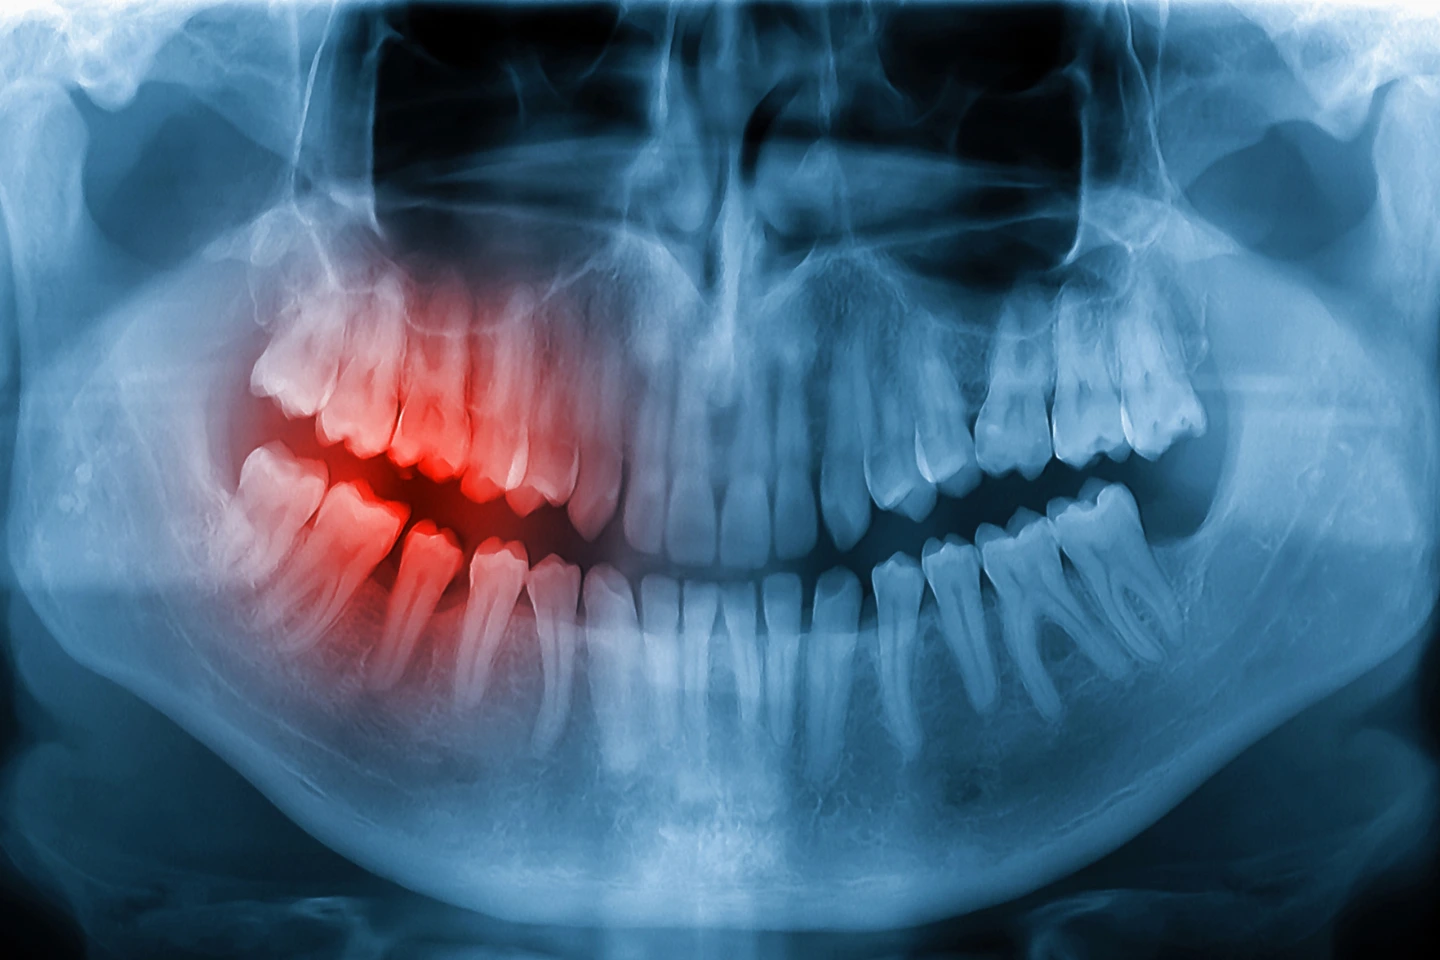

Not all dental X-rays are the same. Dentists use different types of imaging depending on the information they need about your teeth and jaw.

Common types of dental X-rays include:

- Bitewing X-rays: These are the most common type and help dentists detect cavities between teeth and monitor bone levels around the teeth.

- Periapical X-rays: These images show the entire tooth, including the root and surrounding bone. They are often used to detect infections, root problems, or abscesses.

- Panoramic X-rays: This type captures a full view of the mouth, including all teeth, jawbones, and sinuses. It is commonly used for evaluating wisdom teeth, orthodontic planning, and dental implants.

For more advanced diagnostics, dentists may also use 3D cone beam imaging technology to capture highly detailed views of the teeth, bone, and surrounding structures.